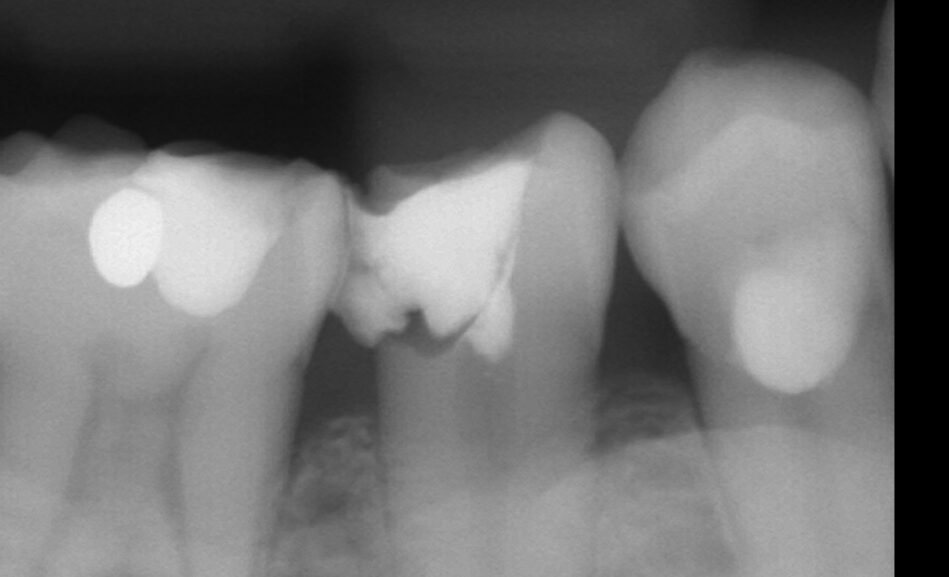

まず、浸潤麻酔を行い、ラバーダム防湿下で丁寧に虫歯を除去していきます。

虫歯を全て除去したら神経が露出しましたので、上部歯髄を切断して新鮮な面を出し、消毒を行いMTAセメントを貼付しました。

この日は1日でMTA治療は終了しました。

その後、3ヶ月経過するも痛みが出なかったためセラミックの被せ物の治療へ移行しました。